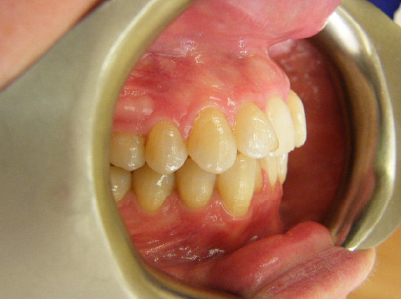

Patient 4: Upper and lower crowding and a deep overbite.